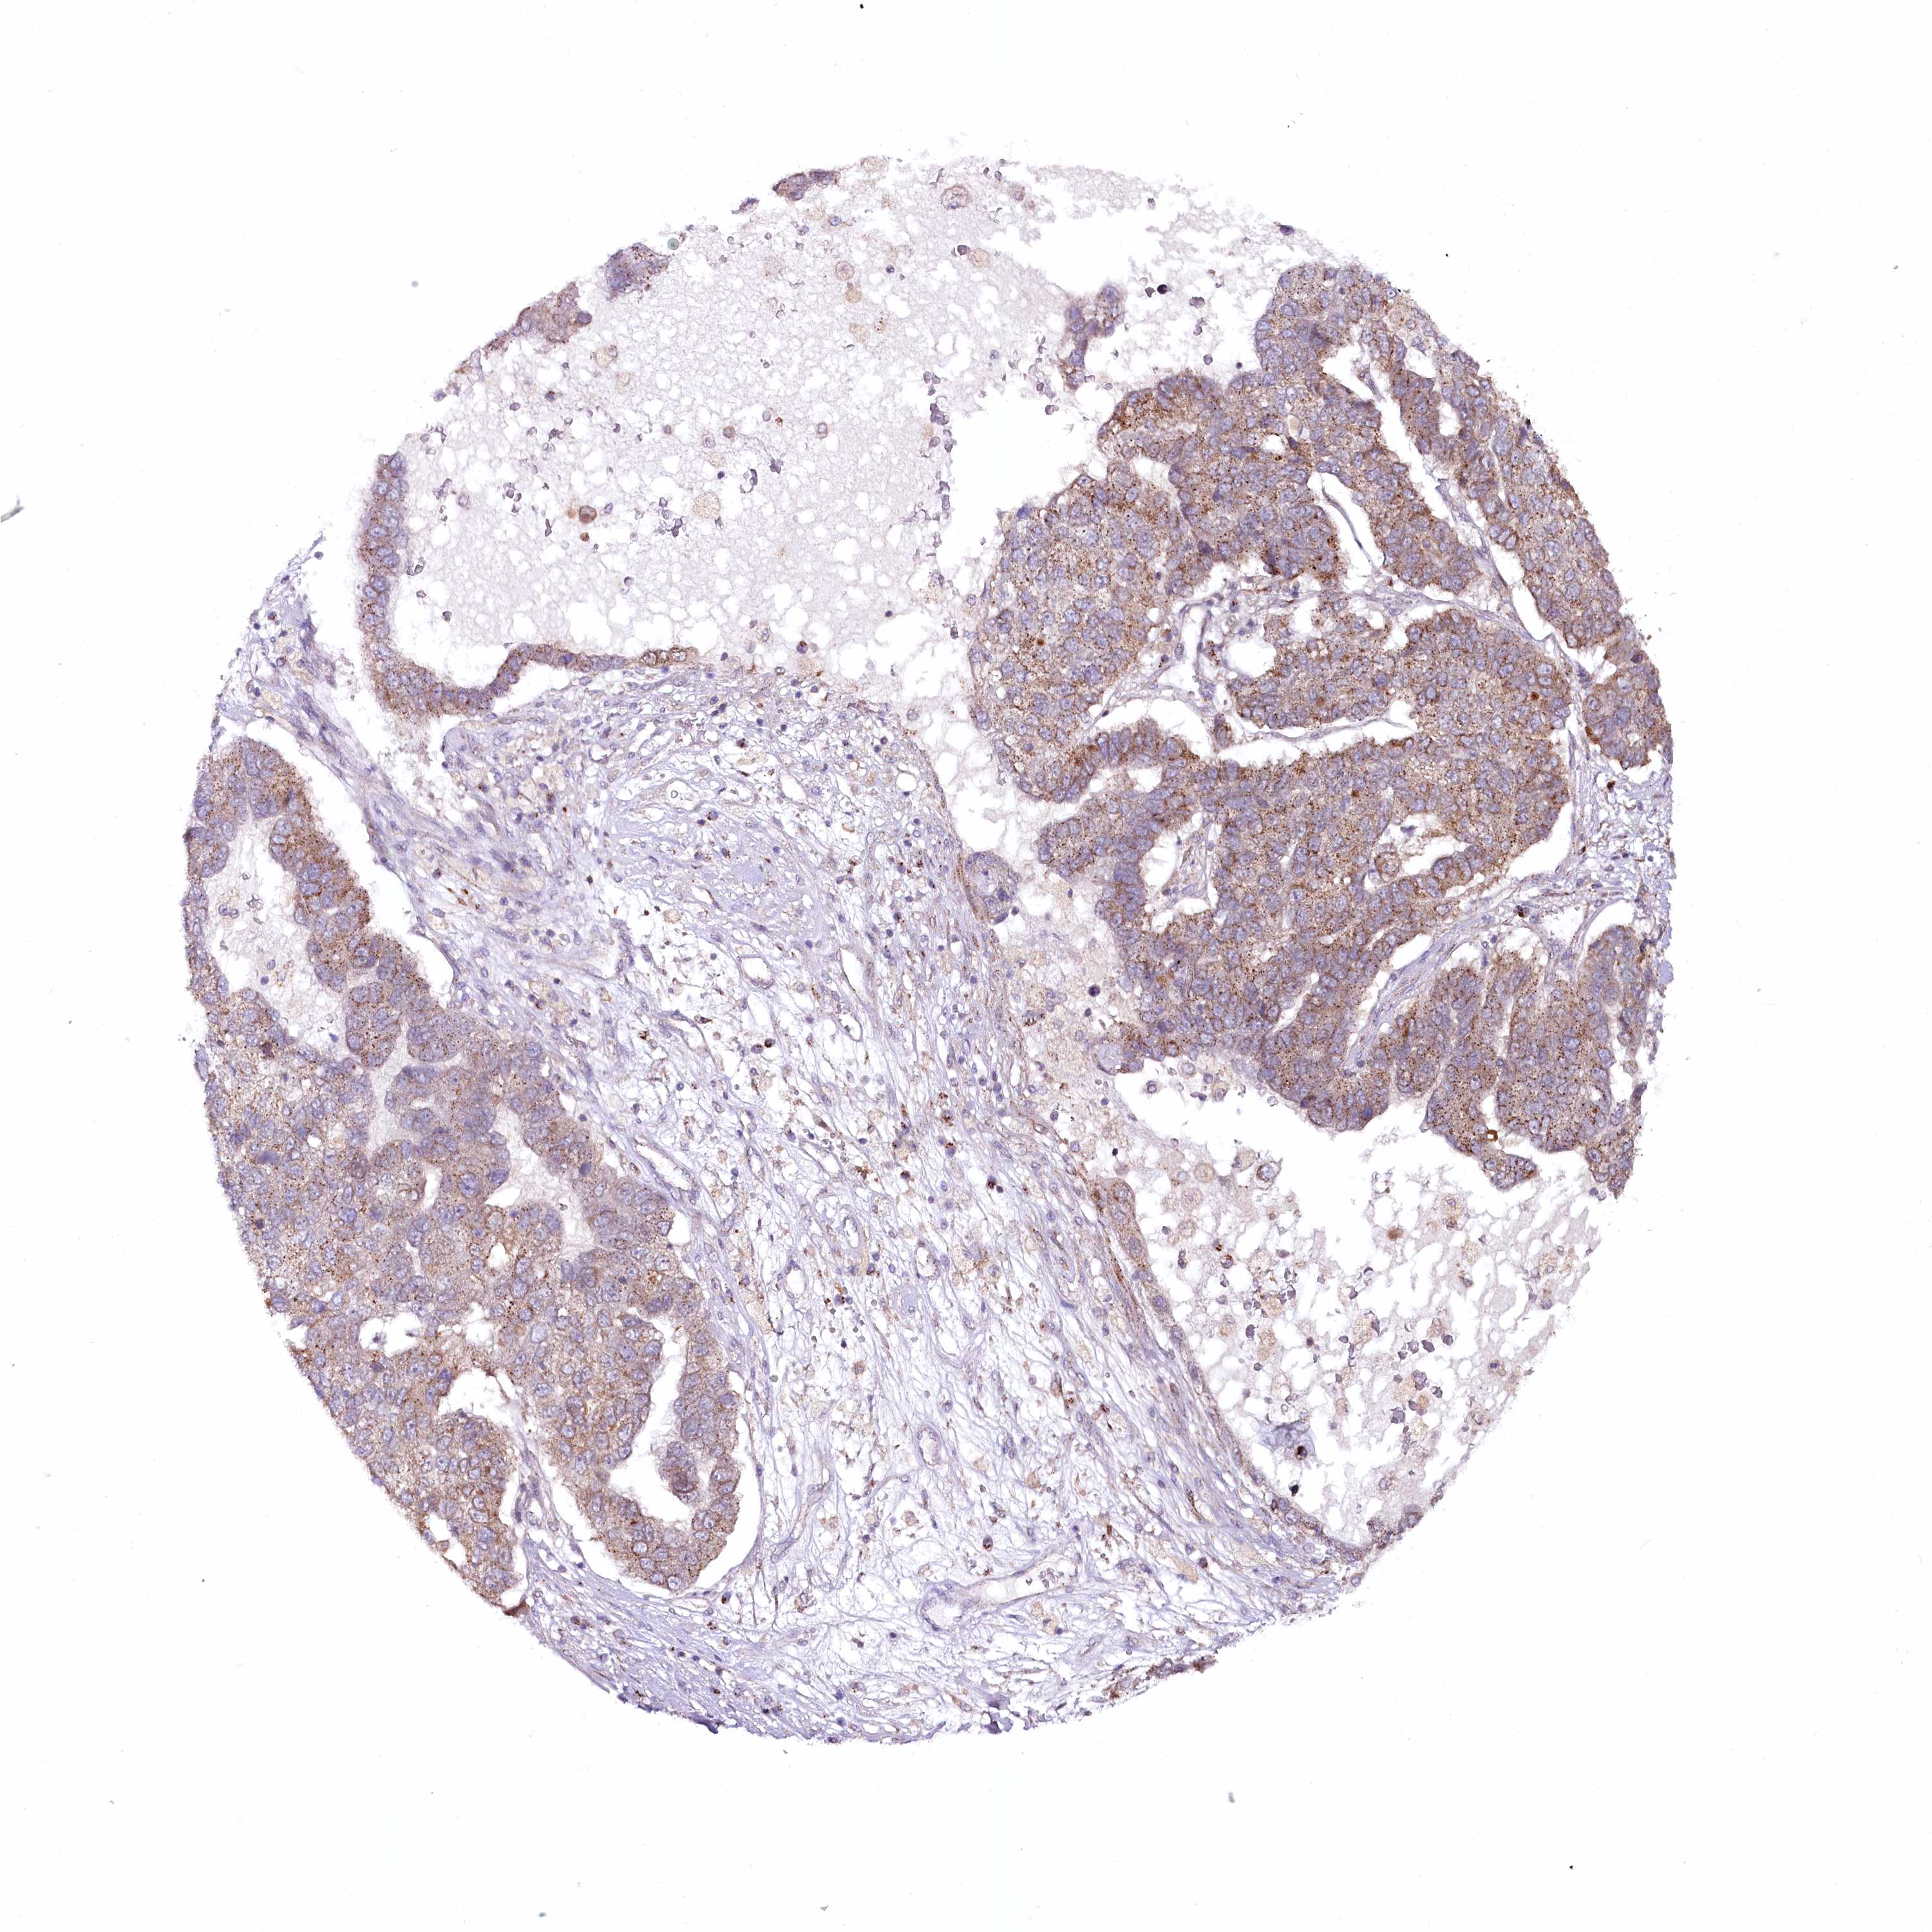

PANCREATIC CANCER - Protein expressioni

A mouse-over function shows sample information and annotation data. Click on an image to view it in a full screen mode. Samples can be filtered based on level of antibody staining by selecting one or several of the following categories: high, medium, low and not detected. The assay and annotation is described here.

Note that samples used for immunohistochemistry by the Human Protein Atlas do not correspond to samples in the TCGA dataset.

Antibody stainingi

Antibody staining in the annotated cell types in the current human tissue is reported as not detected, low, medium, or high, based on conventional immunohistochemistry profiling in selected tissues. This score is based on the combination of the staining intensity and fraction of stained cells.

Each image is clickable and will lead to virtual microscopy that enables deeper exploration of all samples and also displays staining intensity scores, fraction scores and subcellular localization as well as patient and tissue information for each sample.

Antibody HPA037866

Antibody HPA037867

Antibody HPA045712

Staining

High

Medium

Low

Not detected

Intensity

Strong

Moderate

Weak

Negative

Quantity

>75%

75%-25%

<25%

None

Location

Nuclear

Cytoplasmic/membranous

Cytoplasmic/membranous,nuclear

Adenocarcinoma, NOS